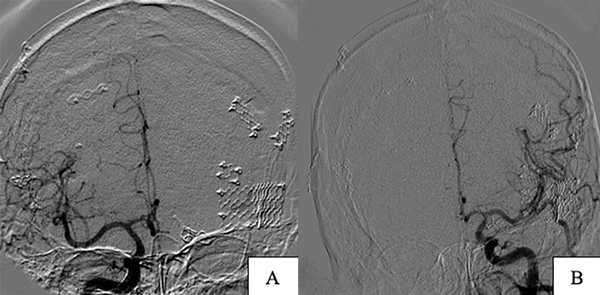

Un año posterior al primer procedimiento se efectúa nueva angiografía digital que no evidencia remanentes de la MAV tratada y correcta exclusión aneurismática (Figura 3), sin cambios respecto al tamaño de la MAV cerebelosa izquierda. Se decidió realizar embolización de esta debido a la negativa del paciente ante una nueva propuesta quirúrgica, pero por el reducido calibre de la arteria aferente no fue posible, decidiéndose finalmente su tratamiento mediante radiocirugía.

Figura 3. Imágenes postoperatorias caso 1, incidencias frente. A) Exéresis de MAV temporal derecha. B) Clipado de aneurisma de bifurcación carotídea izquierdo.